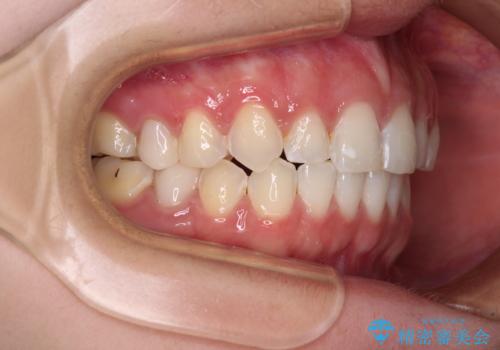

- 前歯の歯列不正を気にして来院された患者様です。

インビザラインでの矯正治療を希望されていましたが、奥歯の咬み合わせがインビザライン単独では改善困難と判断されたので、補助装置を併用することとしました。

まずは裏側の装置やワイヤー矯正を用いて歯列幅の狭い上顎を側方に拡大しつつ全体を後方に移動させ、その後インビザラインにて歯列を整えることとしました。